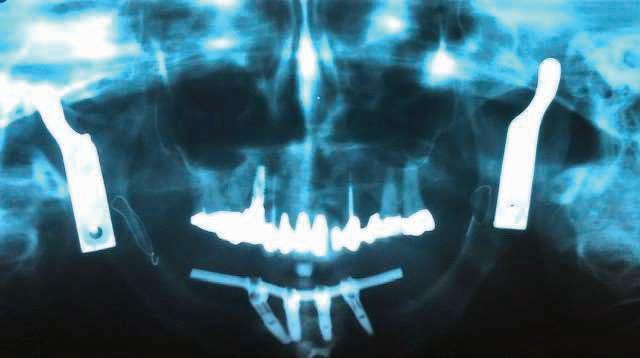

The patient provided a panoramic radiograph taken at an outside clinic prior to the extraction of #1. It revealed an ill-defined radiolucent lesion in the right maxilla extending from the distal of #1 to the anterior segment of the upper right quadrant. The anterior extent was difficult to delineate due to the shadow from the airway. The panoramic radiograph confirmed the patient was missing #2 prior to the extraction of #1. He also provided two upper right molar periapical radiographs. The pre-extraction periapical radiograph showed a destructive radiolucent lesion extending from the distal of #1 to the distal root of #3. The mesial root of #1 and the apex of the distal root of #3 demonstrated external root resorption. The postextraction periapical radiograph showed irregular root apices of #3 and an expansile radiolucency extending from the edentulous area distal of #3 to its mesial root. A new panoramic radiograph was obtained in the predoctoral urgent care dental clinic. This radiograph revealed a destructive radiolucency involving the right maxilla distal and apical to #3 with destruction of the inferior wall of the maxillary sinus (Figure 2).

Figure 2. Panoramic radiograph revealed a destructive radiolucency involving the maxilla distal and apical to #3 with destruction of the inferior wall of the maxillary sinus.